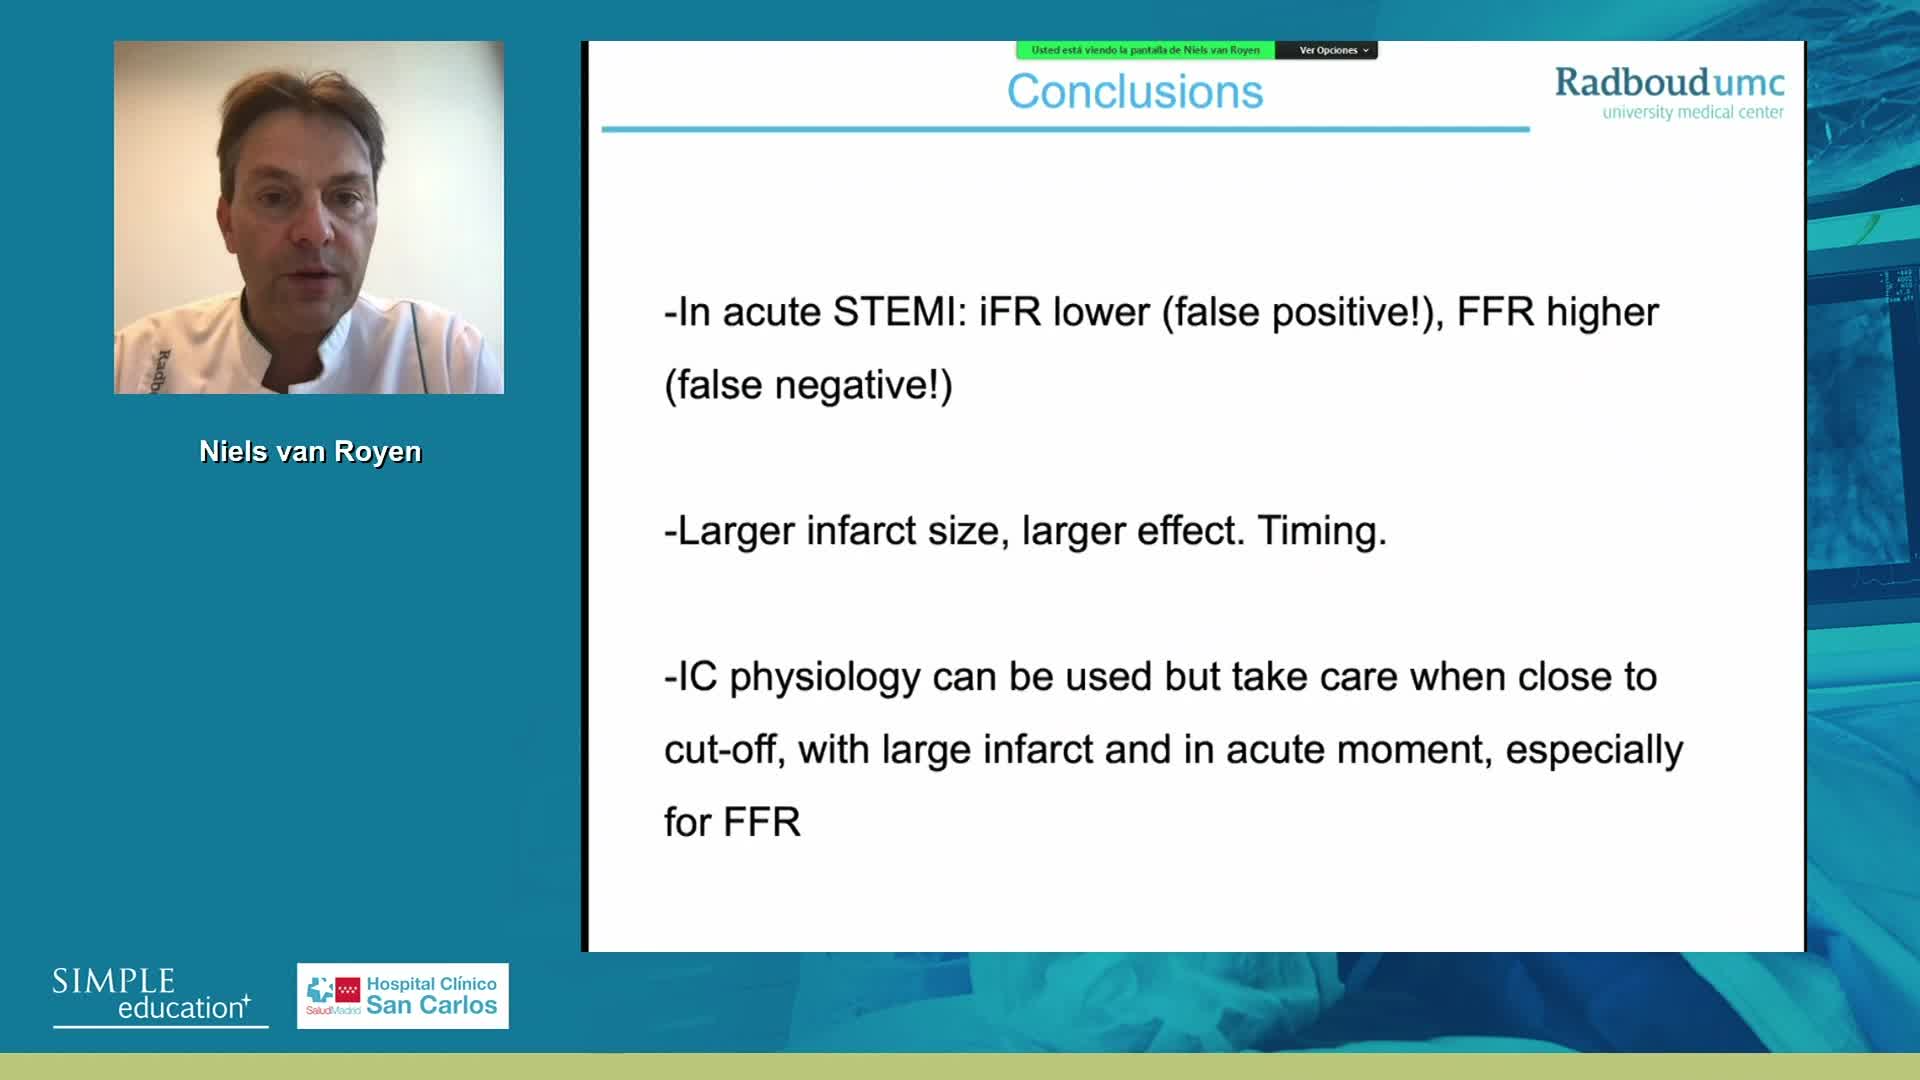

Can I Measure Coronary Chysiology in Patients with Acute Coronary Syndroms, Atrial Fibrillation, Congestive Heart Failure, Paced Rhythms, Cardiogenic shock and Aortic Stenosis?

Can I Measure Coronary Chysiology in Patients with Acute Coronary Syndroms, Atrial Fibrillation, Congestive Heart Failure, Paced Rhythms, Cardiogenic shock and Aortic Stenosis?

Can I Measure Coronary Chysiology in Patients with Acute Coronary Syndroms, Atrial Fibrillation, Congestive Heart Failure, Paced Rhythms, Cardiogenic shock and Aortic Stenosis?

ABC for using Coronary Physiology in Aortic Stenosis, Primary Percutaneous Coronary Intervention (PPCI)/ACS, Muscle Bridges and Atrial Fibrillation - Dr Ricardo Petraco